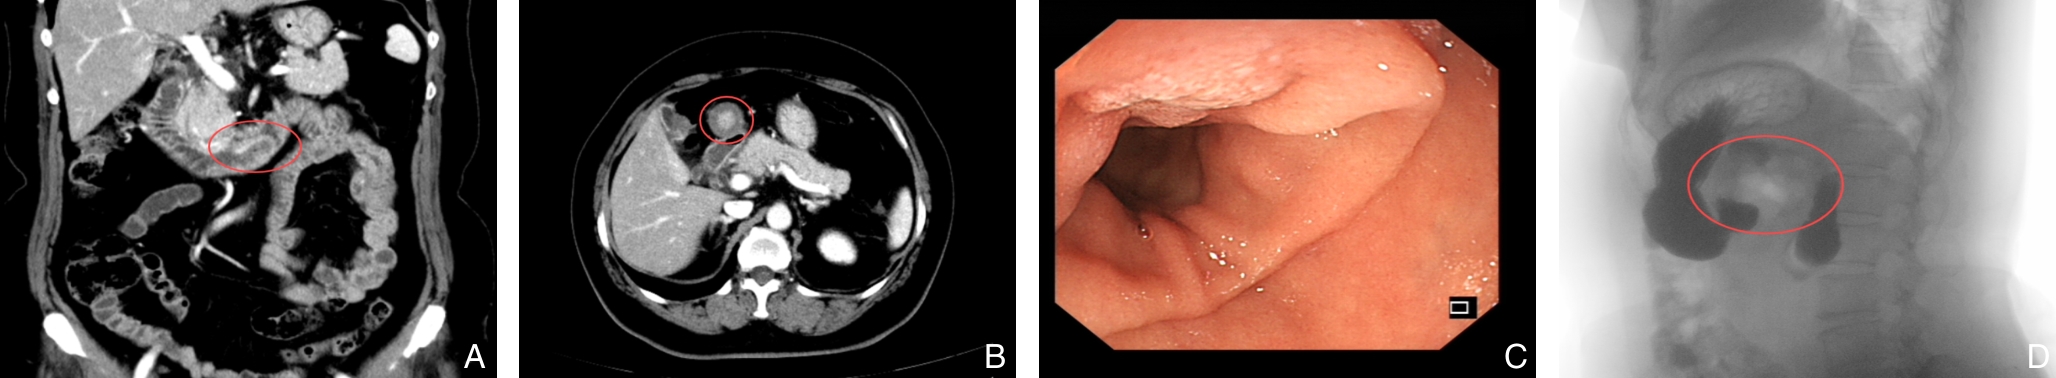

摘要:背景与目的 急性胰腺炎(AP)是一种由多种因素引起的胰腺急性炎症反应,以胰酶异常激活及自身消化为主要特征。尽管常见病因为胆石症、高脂血症及饮酒,但部分患者的病因罕见且诊断延迟,易导致复发及误治。本文通过分析4例以AP为首发症状的少见病因病例,并结合文献复习,总结其诊断思路与治疗经验,为临床鉴别诊治提供参考。方法 回顾性分析中南大学湘雅三医院2021年11月—2024年9月收治的4例以AP为首发表现的少见病因患者的临床资料,结合国内外相关文献,探讨其病因特征、诊断要点及治疗策略。结果 4例患者的病因为胰腺导管内乳头状黏液性肿瘤、胰腺神经内分泌瘤、胰腺癌及十二指肠肠套叠。所有病例初诊时均表现为不明原因AP。经系统评估后,3例患者接受手术根治,术后恢复良好;1例患者因胰腺癌确诊较晚,仅行姑息性治疗,3个月后死亡。结论 少见病因所致的AP临床表现与常见类型相似,早期识别难度大。针对反复发作或原因不明的AP,应重视病因追溯,充分利用影像学及内镜检查手段明确诊断。对可手术病变应积极干预,以减少复发并改善预后。

摘要:背景与目的 复发性急性胰腺炎(RAP)病因复杂,其中由寄生虫感染引起者极为罕见。胰腺阔盘吸虫侵入胰管导致梗阻并诱发RAP,目前国内尚无报道。本研究通过1例确诊病例,结合文献复习,探讨其临床特征、诊断难点及防治要点。方法 回顾分析湖南师范大学附属第一医院2023年收治的1例胰腺阔盘吸虫致RAP患者的临床资料,包括影像学、手术及病理学结果,并综述国内外相关文献。结果 患者为59岁女性,表现为反复上腹痛4年。影像学提示胰体尾部多囊性病变并胰管扩张,术前被考虑为胰管内乳头状黏液性肿瘤。行腹腔镜胰体尾及脾切除术后,病理证实导管内存在吸虫虫体及虫卵,最终确诊为胰腺阔盘吸虫感染。术后恢复良好,随访1年未再发胰腺炎。结论 胰腺阔盘吸虫是RAP罕见的病因,临床及影像学表现缺乏特异性,易误诊为胰腺囊性肿瘤。对于病因不明的RAP,尤其是有食用生食或野味史的患者,应重视寄生虫学检查,如粪便虫卵及血清抗体检测,以早期确诊并指导治疗。